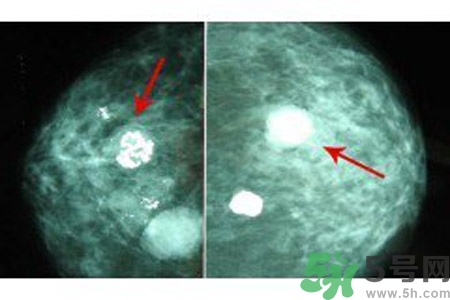

乳腺鈣化數(shù)目

良性鈣化一般數(shù)目少,顆粒粗大。惡性病變表現(xiàn)為數(shù)目多,甚至無(wú)法計(jì)數(shù),如泥沙樣鈣化、成簇的針尖樣鈣化。但有時(shí)也可表現(xiàn)為數(shù)量較少,數(shù)顆或數(shù)十顆,數(shù)目少的惡性鈣化常見(jiàn)于分叉狀、小桿狀。1972年Woife提出15~20個(gè)/cm2個(gè)鈣化點(diǎn),即可判斷為惡性鈣化。

了解鈣化部位應(yīng)強(qiáng)調(diào)多方位、多角度觀察。良性鈣化灶,多發(fā)生在纖維組織、脂肪、血管、大汗腺、皮膚等乳腺間質(zhì)內(nèi),乳腺實(shí)質(zhì)內(nèi)少見(jiàn)。惡性鈣化則多發(fā)生于乳腺實(shí)質(zhì)內(nèi),泥沙樣鈣化多發(fā)生在乳腺小葉腺泡內(nèi),小桿狀鈣化多發(fā)生在導(dǎo)管內(nèi),小叉狀鈣化則多位于末支小導(dǎo)管內(nèi)。

乳腺鈣化與腫塊的關(guān)系

鈣化可與腫塊并存,也可獨(dú)立存在;既可發(fā)生在病變內(nèi),也可獨(dú)立于腫塊之外。90%的導(dǎo)管原位癌是通過(guò)X線鉬靶照片發(fā)現(xiàn)的,且僅以乳腺內(nèi)鈣化作為惟一的表現(xiàn)形式。這是由于原位癌中央發(fā)生不規(guī)則壞死引起的鈣鹽在導(dǎo)管內(nèi)沉積或腫瘤細(xì)胞分泌而呈形態(tài)各異的的表現(xiàn)。